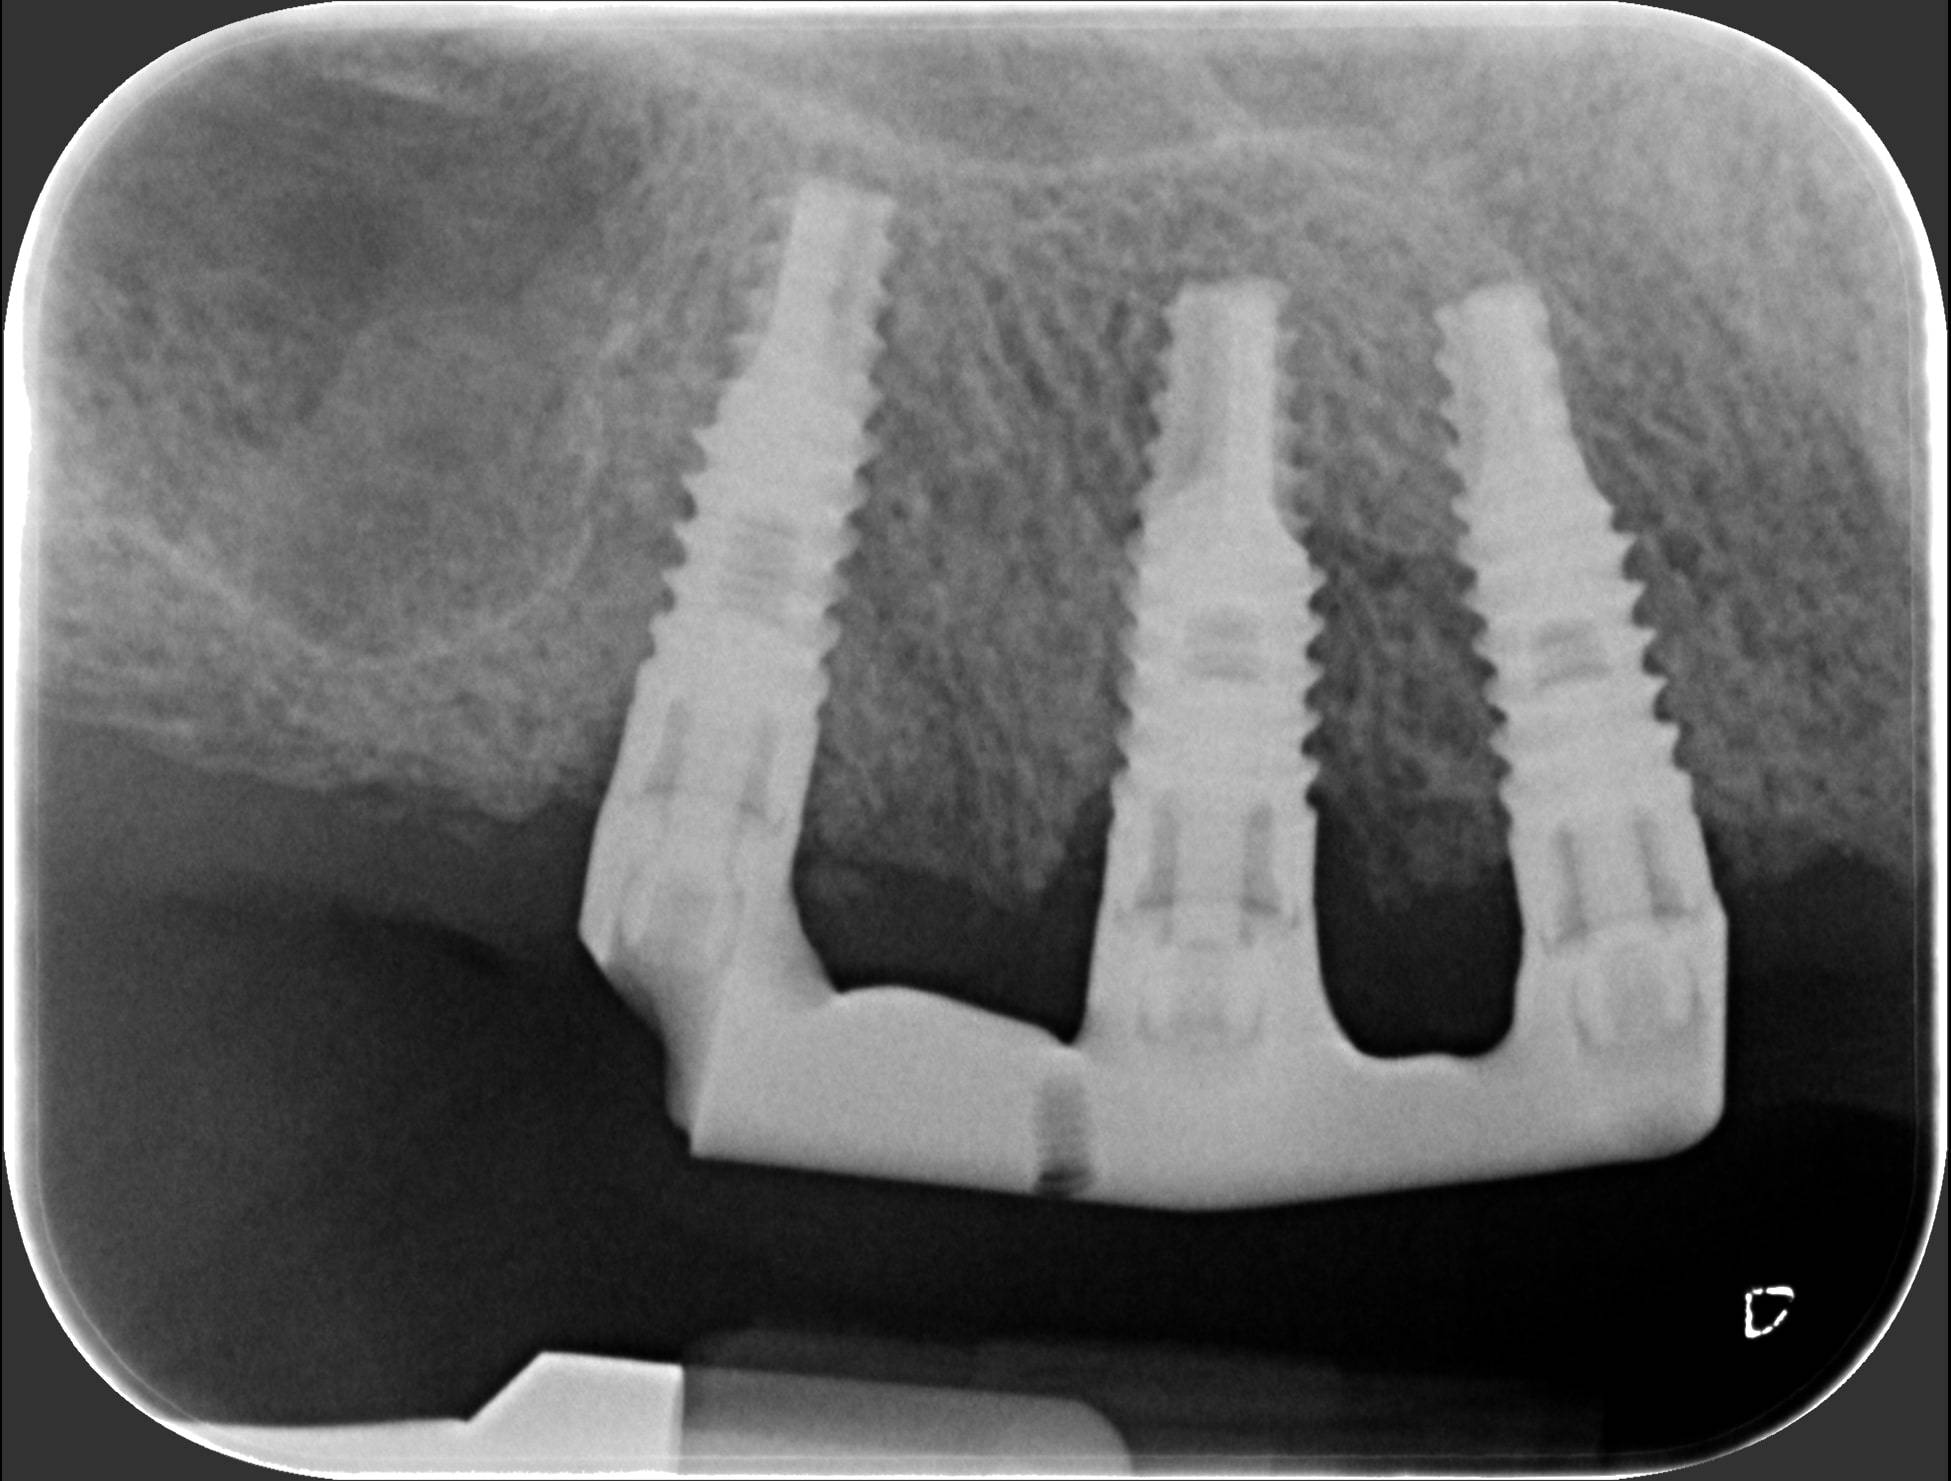

Generalmente devono trascorrere alcuni mesi tra l’intervento chirurgico di inserimento di un impianto e la realizzazione della protesi da fissare ad esso.

In questo lasso di tempo, nel quale l'impianto è sommerso sotto la gengiva e si avvia il processo di guarigione ossea, si realizza l'osteointegrazione, ovvero un intimo contatto fra l’osso e la superficie biocompatibile in titanio dell’impianto.

Tuttavia, in alcuni casi selezionati, è possibile protesizzare gli impianti subito dopo il loro posizionamento, nel giro di pochi giorni o addirittura nel corso della stessa seduta: questa tecnica è definita “carico immediato” e consente al paziente di entrare in Studio con la sua vecchia dentiera e di uscire il giorno stesso con una protesi fissa.

Una tecnica recente e molto apprezzata è l’implantologia computer guidata. L’anatomia della zona da operare è studiata con la Tomografia Computerizzata, simulando al computer, con un software di alta precisione 3D, il posizionamento degli impianti. Sulla base dei dati elaborati dal software si realizza in laboratorio una mascherina chirurgica che guiderà gli strumenti e gli impianti nella corretta posizione nell’osso del paziente, rendendo l’intervento più sicuro e veloce.